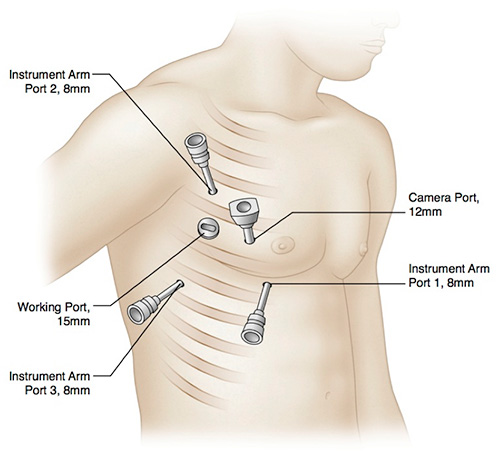

Totally endoscopic robotic septal myectomy ports

While the standard surgical septal myectomy is performed via sternotomy, NewYork-Presbyterian/Weill Cornell offers a totally endoscopic robotic procedure that allows for both septal myectomy and augmentation of the anterior leaflet. The many potential advantages to this minimally invasive approach include exquisite visualization of the septum from the aortic valve to the apex of the heart. The endoscopic robotic approach also allows for easier access to mitral valve subchordal structures and the avoidance of residual postoperative gradients due to inadequate myectomy by enlarging both sides of the left ventricular outflow tract (LVOT).

Robotic Septal Myectomy